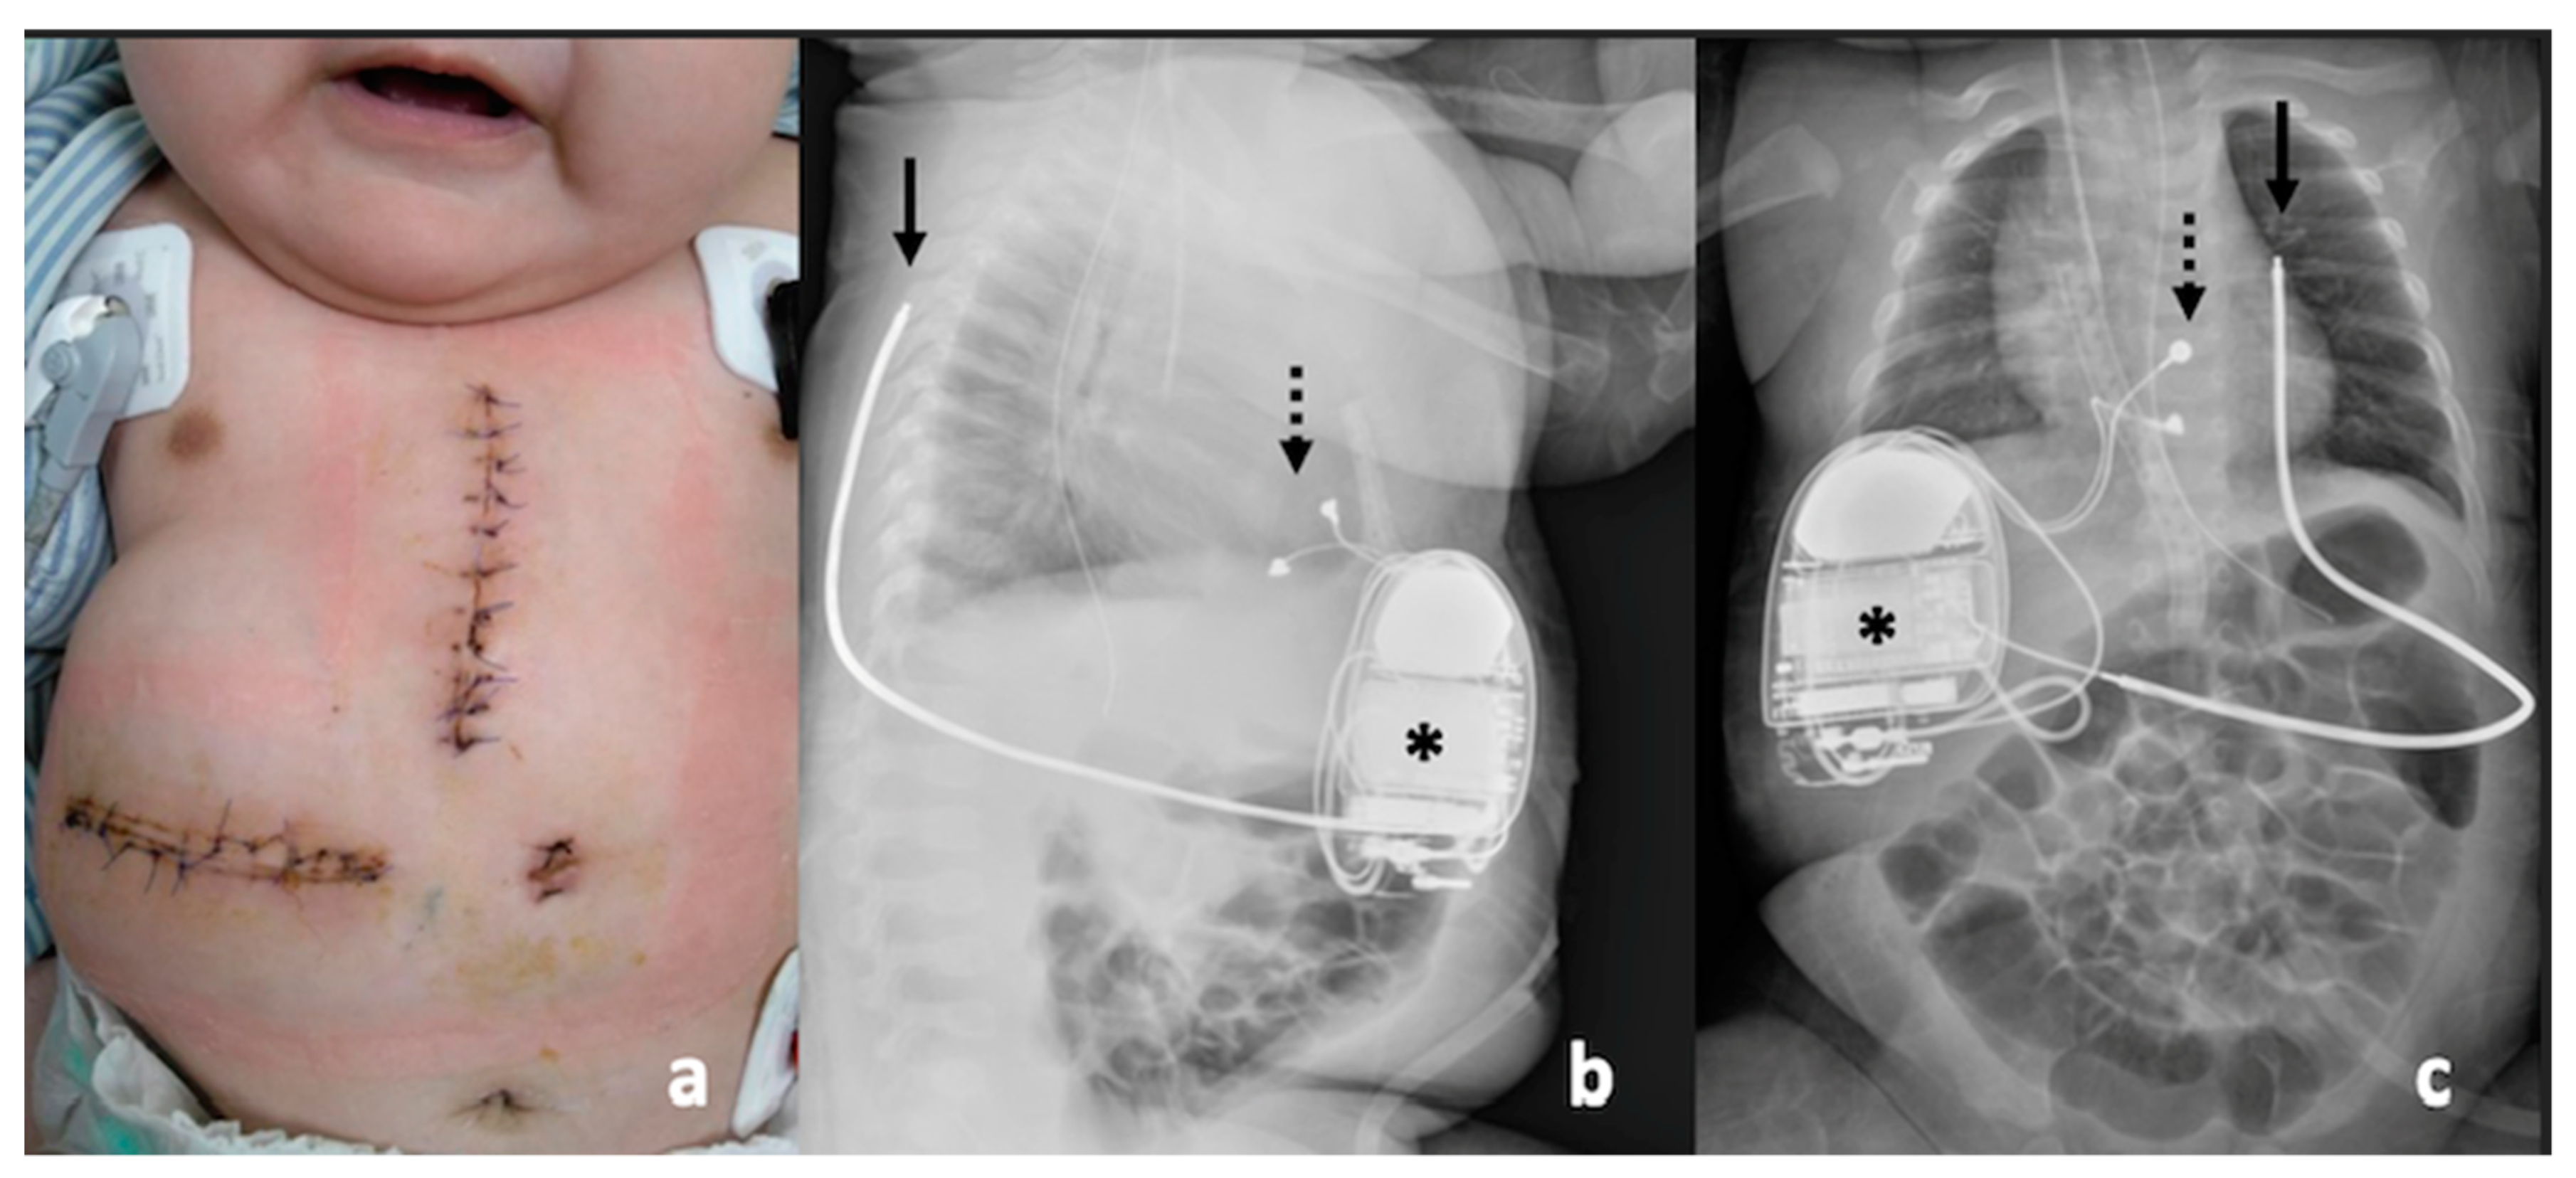

2. Case Report

3.5. ICD Implantation in Infancy